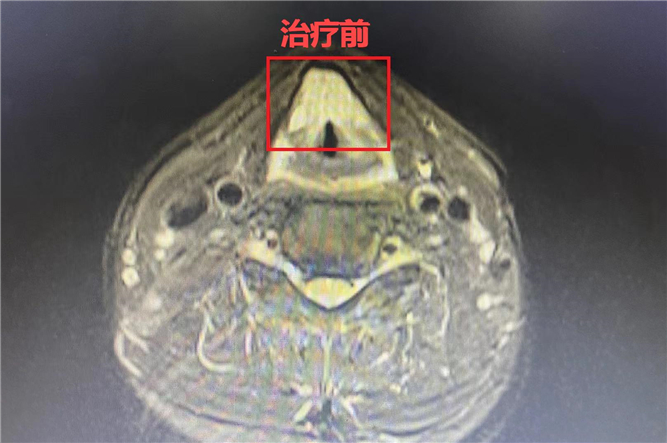

▲治療前

這次復(fù)發(fā)后采取放療的治療方式,在聲帶功能維持正常的基礎(chǔ)上,實現(xiàn)“消瘤不消聲”,保持發(fā)音功能,治療效果很好,還保證了生活質(zhì)量!